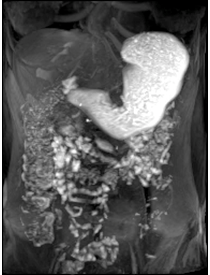

Magnetic Resonance Imaging of the Brain and the Upper Gastrointestinal Tract in Healthy Volunteers and Patients with Gastroparesis

Primary Outcomes Measured: Compare 3D--dimensional gastric peristalsis progression before & after test meals in healthy volunteers and patients with gastroparesis

- Compare colored 3-D heat map of stomach contraction frequency before & after test meals in healthy volunteers and patients with gastroparesis

- Compare pylorus mean opening diameter before & after test meals in healthy volunteers and patients with gastroparesis